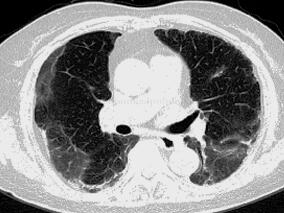

1小时条评论一、病史摘要 患者,男性,27岁,工人,因服食百草枯后反复呕吐、咳痰6天,气促2天于2012年3月10日入住我院。患者2012年3月4日因与家人争吵后服食百草枯一口(量不详)随即吐出,当即出现反复恶心、呕吐、反酸症状,非喷射性,继而出现持续性咳嗽、咳痰,为黄白色浓...